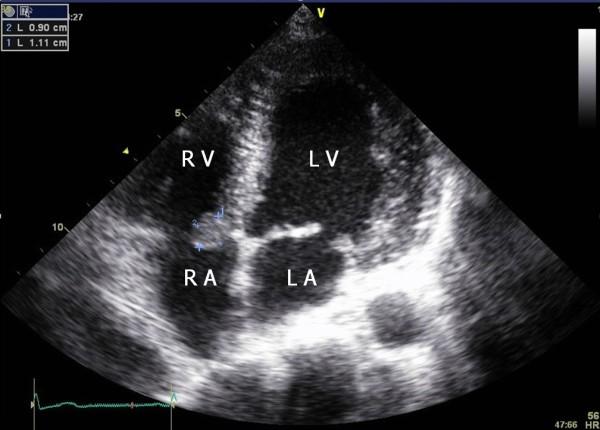

A 25-year-old woman with a history of kidney transplantation for lupus nephritis was referred for the evaluation and management of a mass incidentally found on echocardiography. An oval and pedunculated mass attached to the tricuspid valve was managed with nonsurgical treatment. No symptoms and complications attributable to the mass developed. Three years later, the size of the mass decreased. Here we report the case of a probable cardiac papillary fibroelastoma (PFE), a mobile mass, with a stalk on the septal leaflet of the tricuspid valve that was managed for three years without surgical treatment.